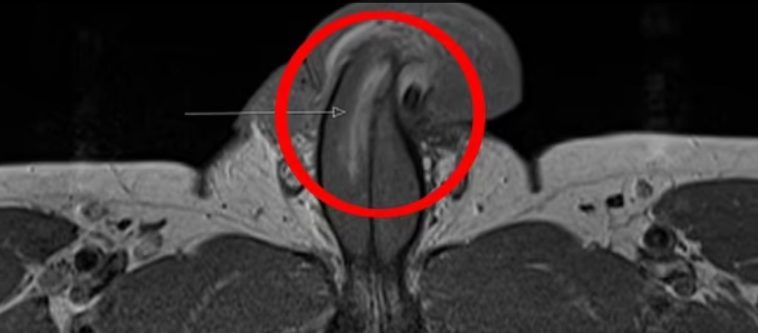

- Ο άνδρας, σύμφωνα με πληροφορίες, βρέθηκε σε κατάσταση έντονου πόνου μετά από ερωτική επαφή με υπέρβαρη συνοδό πολυτελείας. Όπως ανέφερε, κατά τη διάρκεια της πράξης, “κάτι δεν πήγε καλά” και το πέος του έδειχνε να έχει υποστεί ρήξη.

Οι γιατροί του νοσοκομείου πραγματοποίησαν λεπτή χειρουργική επέμβαση για να αποκαταστήσουν τη ζημιά.